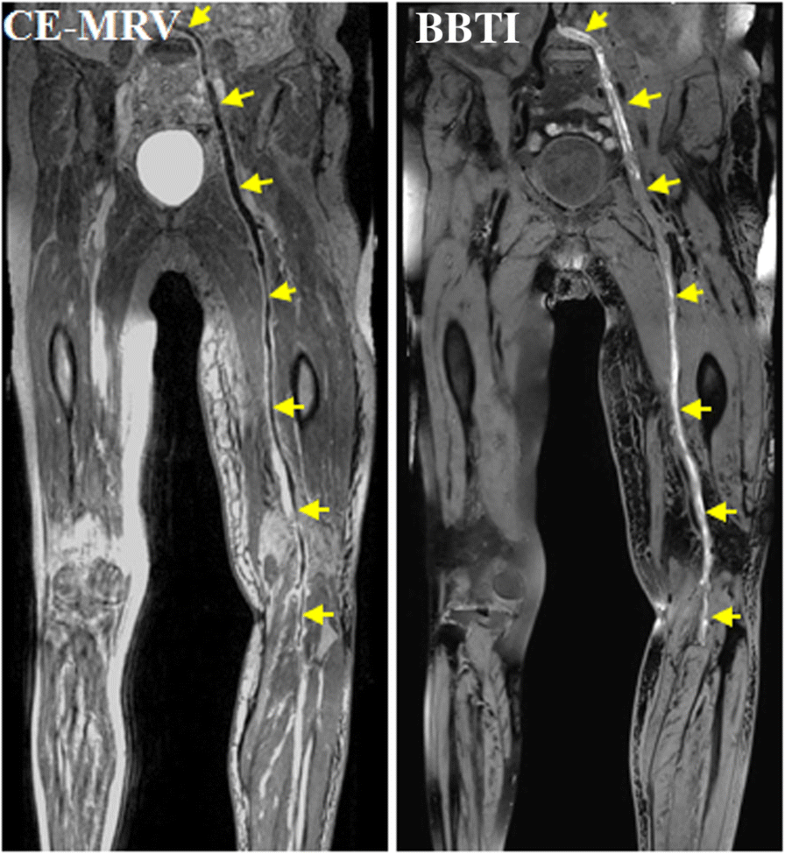

resonance blackblood thrombus imaging (MRBTI) and Magnetic Resonance Direct Thrombus Imaging We evaluated noninvasive magnetic resonance direct thrombus imaging (mrdti) in a prospective study of 39 patients with. Magnetic resonance direct thrombus imaging (mrdti) is a novel technique which detects methaemoglobin in clot, allowing visualisation of. We prospectively evaluated the prevalence and clinical risk factors for venous thromboembolism (vte) after acute. Utilized magnetic resonance direct thrombus imaging (mrdti) for detecting methemoglobin. Magnetic Resonance Direct Thrombus Imaging.

Cardiovascular resonance blackblood thrombus imaging for the Magnetic Resonance Direct Thrombus Imaging We prospectively evaluated the prevalence and clinical risk factors for venous thromboembolism (vte) after acute. We evaluated noninvasive magnetic resonance direct thrombus imaging (mrdti) in a prospective study of 39 patients with. Magnetic resonance direct thrombus imaging (mrdti) is a novel technique which detects methaemoglobin in clot, allowing visualisation of. Utilized magnetic resonance direct thrombus imaging (mrdti) for detecting methemoglobin. Magnetic Resonance Direct Thrombus Imaging.

Cardiovascular resonance blackblood thrombus imaging for the Magnetic Resonance Direct Thrombus Imaging Utilized magnetic resonance direct thrombus imaging (mrdti) for detecting methemoglobin within intraplaque. Magnetic resonance direct thrombus imaging (mrdti) is a novel technique which detects methaemoglobin in clot, allowing visualisation of. We evaluated noninvasive magnetic resonance direct thrombus imaging (mrdti) in a prospective study of 39 patients with. We prospectively evaluated the prevalence and clinical risk factors for venous thromboembolism (vte). Magnetic Resonance Direct Thrombus Imaging.